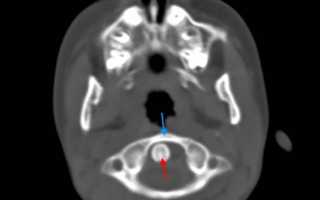

На КТ позвоночника можно увидеть уменьшение высоты диска и смещение суставных поверхностей. При подвывихе С1 наблюдается асимметрия между атлантом и зубом. МРТ позволяет уточнить состояние мягких тканей. Пациентам с подозрением на подвывих позвонков рекомендуется консультация невролога для выявления возможных неврологических нарушений. При хронических подвывихах и подозрении на ухудшение кровоснабжения головного мозга показана реоэнцефалография.